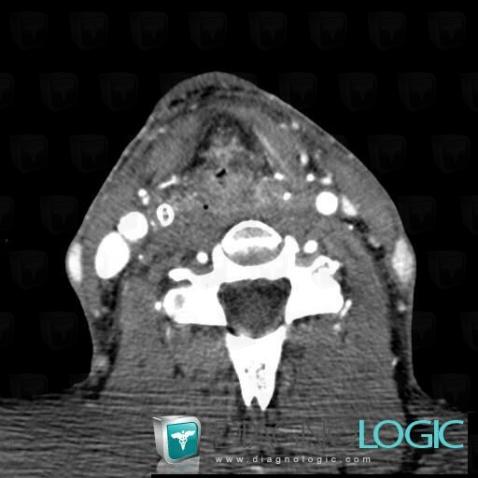

Postradiation edema, Pharyngolarynx, CT

Here is the specific information in the key image above:

- Diagnosis Postradiation edema, Location(s) Pharyngolarynx, with gamuts